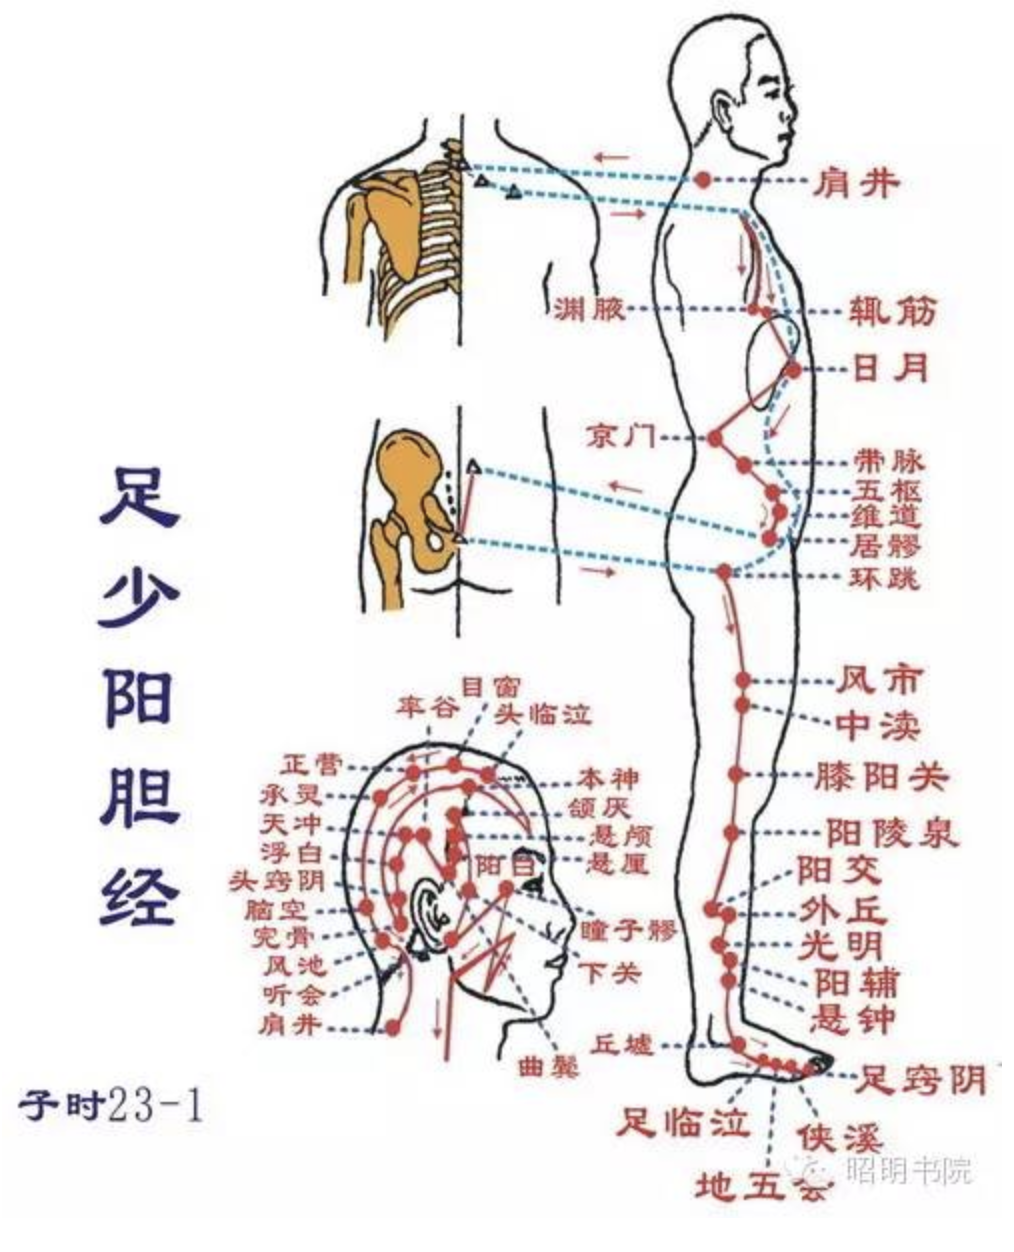

【(十一)足少阳胆经(图 10-29-1)】

1、时辰 子时 23 ~ 1

2、歌诀 少阳足经瞳子髎,四十四穴行迢迢,听会上关颌厌集,悬颅悬厘曲鬓翘,率谷天冲浮白次,窍阴完骨本神邀,阳白临泣木窗辟,正营承灵脑空摇。风池肩井渊腋部,辄筋日月京门标,带脉五枢维道续,居髎环跳风市招,中渎阳关阳陵泉,阳交外邱光明宵,阳辅悬钟邱墟外,临泣地五会侠溪,第四指端窍阴毕。

3、经脉循行 起于目外眦(瞳子髎),向上到额角,返回下行至耳后,沿颈部向后交会大椎穴,再向前入缺盆部,入胸过膈,联络肝脏,属胆,沿胁肋部,出于腹股沟,经外阴毛际,横行入髋(kuān)关节(环跳)。

耳后支部:从耳后入耳中,出走耳前,到目外眦处向后向下经颊部会合前脉与缺盆部。下行腋部,沿侧胸部,经季肋和前脉会于髋关节后,再向下沿大腿外侧,行于足阳明和足太阳经之间,经腓(féi)骨前直下到外踝前,进入足第 4 趾外侧端(足窍明)。

足背部支脉:从足临泣处分出,沿第 1、2跖骨之间,至大趾端(大敦)与足厥阴经相接。

4、主要病候 口苦、目眩、疟疾、头痛、颌痛、目外眦痛、缺盆部、腋下、胸胁、股及下肢外侧、足外侧痛等。

5、主治概要 主治侧头、目、耳、咽喉病、神志病、热病及经脉循行部位的其他病证。